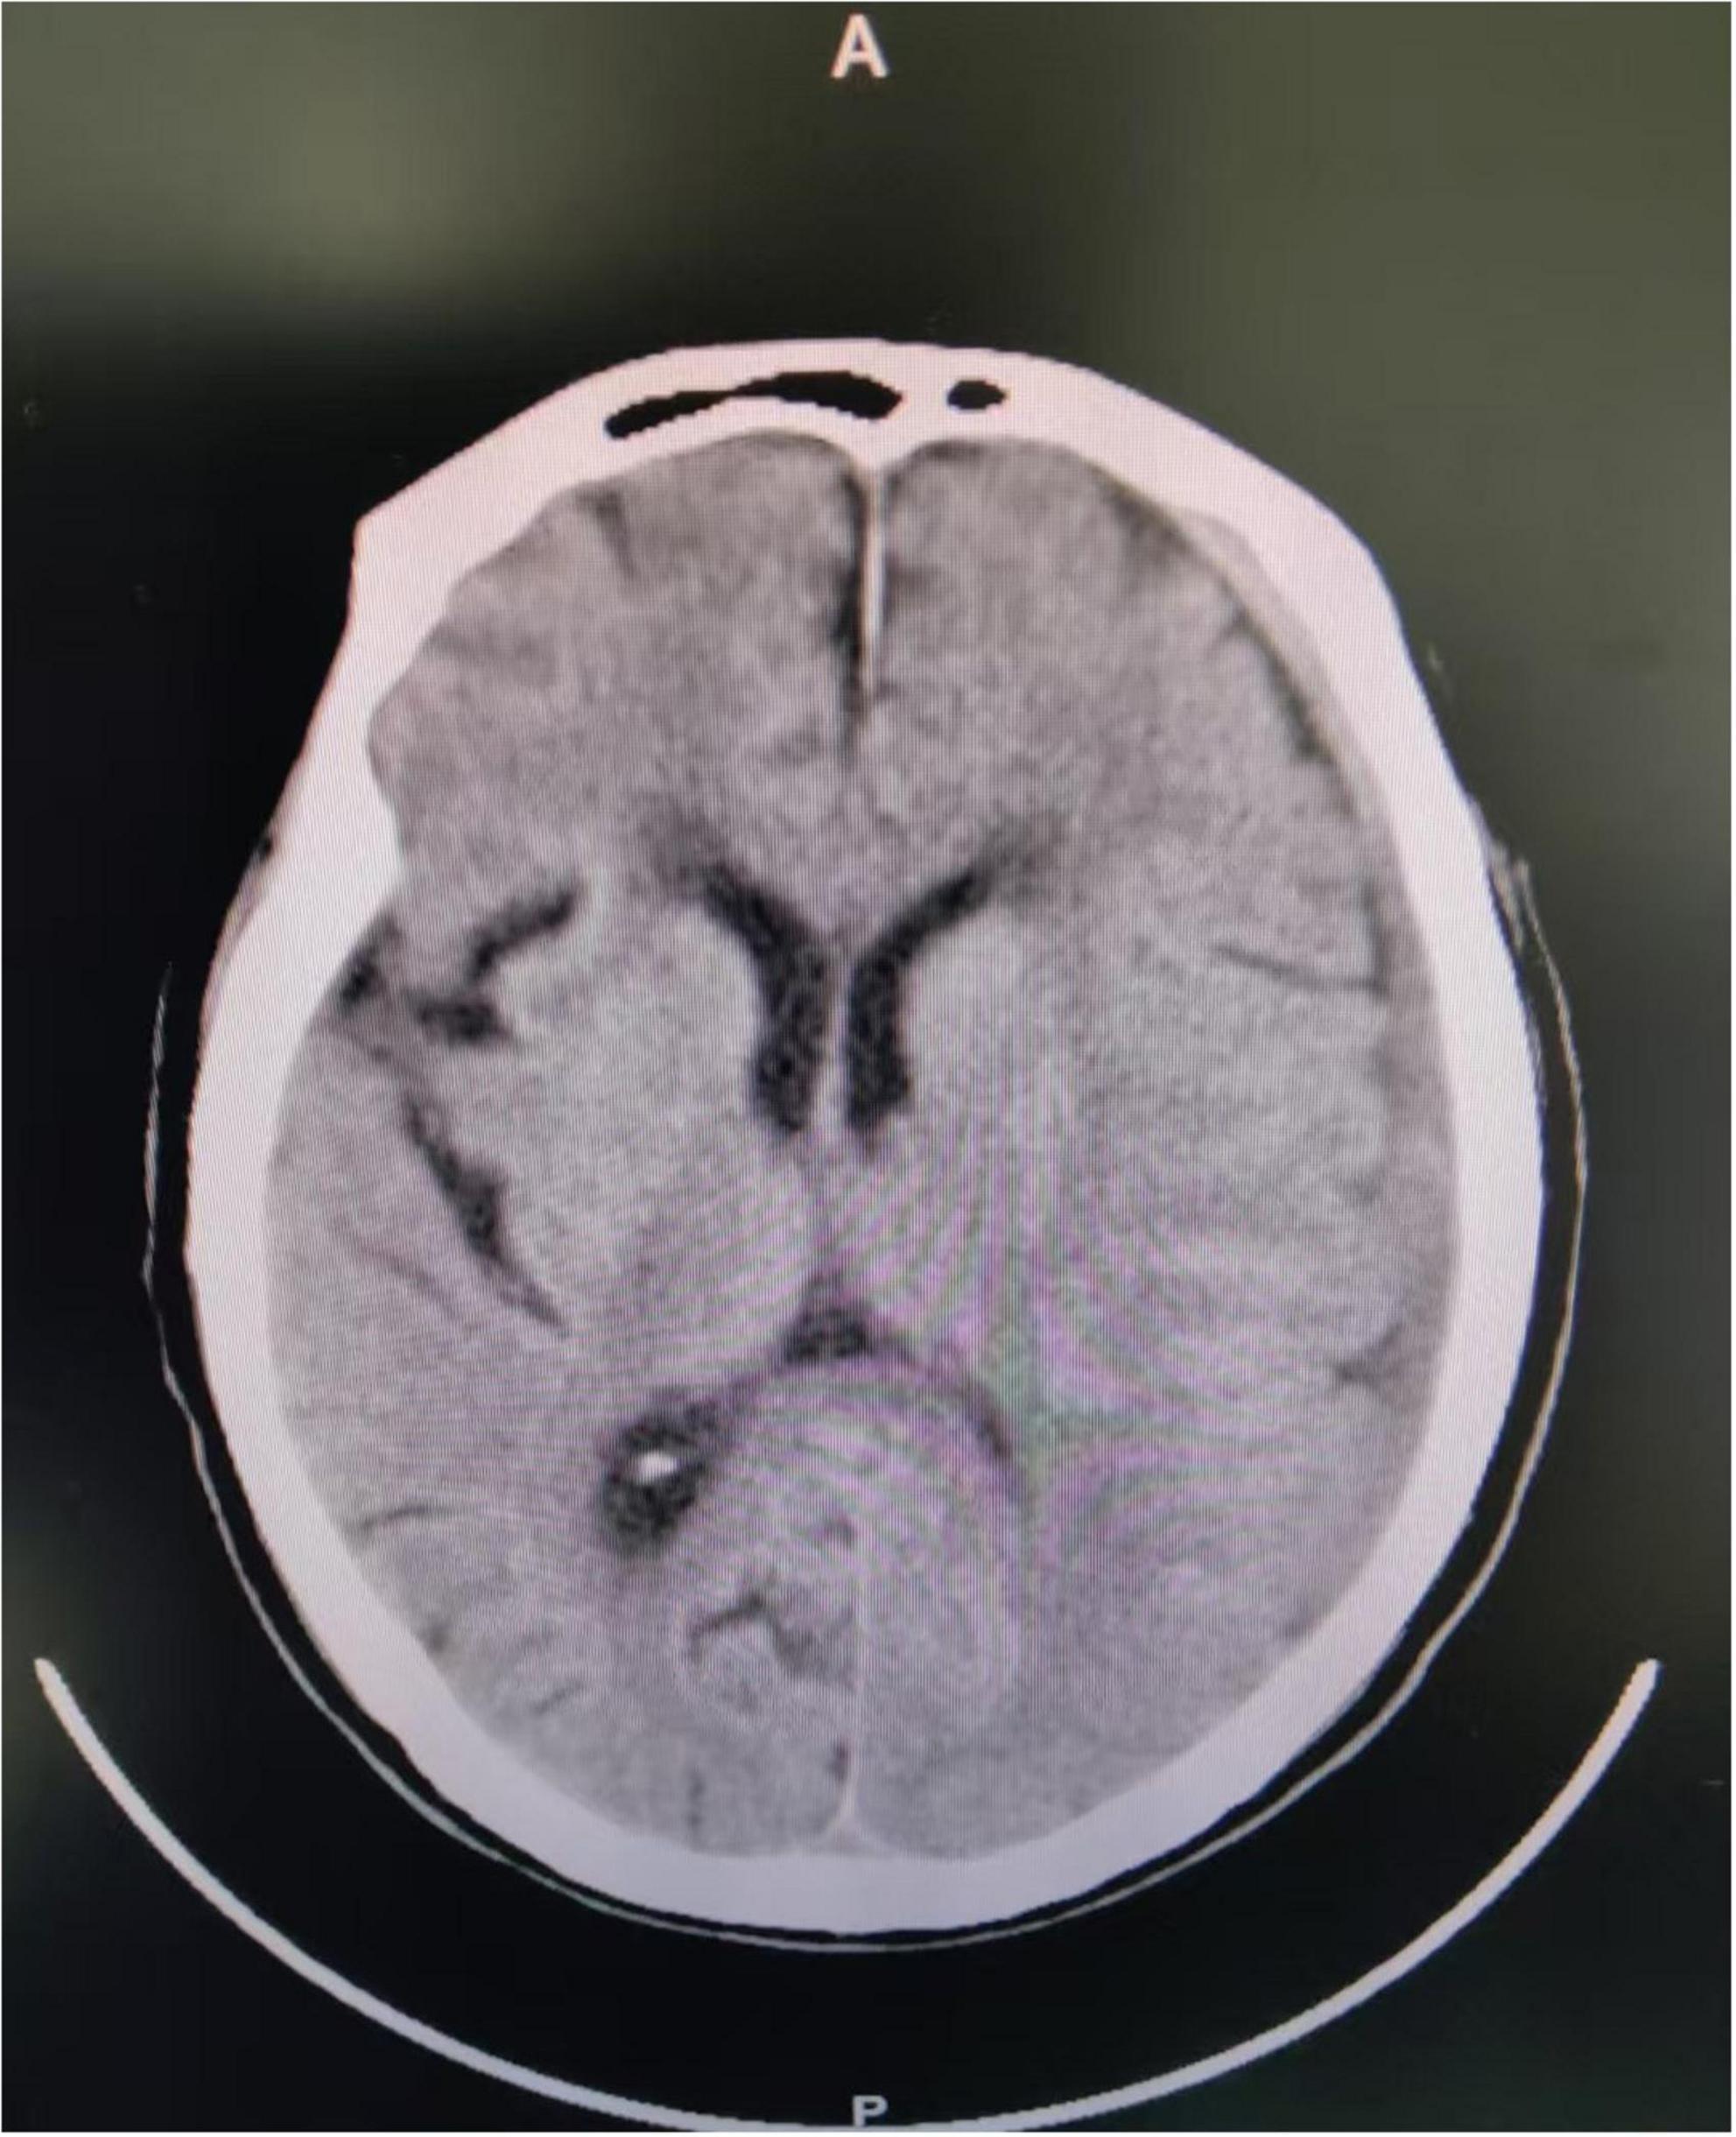

In April 2025, a 75-years-old male patient was admitted to the department of infectious diseases due to a 40-days history of fever. His past medical history was negative for tuberculosis, hematological disorders, or rheumatological diseases. He was a retired civil servant with no clinical background involving agricultural work, poultry contact, or consumption of unpasteurized meat or dairy products. Seven days prior to admission, he had been involved in a traffic accident, sustaining a mild impact to the frontal region of his head. After injury, he did not show any symptoms suggestive of a cerebrospinal fluid (CSF) leak, such as rhinorrhea or otorrhea. Since the impact to the head might have been mild, an initial head CT scan performed at a local hospital revealed only a minimal subdural hematoma without any radiological evidence of a skull base fracture (Figure 1), and consequently, no surgical intervention was undertaken.

FIGURE 1

The patient’s brain CT examination after the car accident showed a small left subdural hematoma.